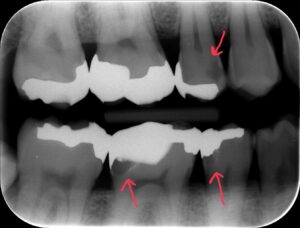

下の参考写真をご覧ください。パノラマエックス線写真というのは、日本の歯科医院でよく撮影されるものです。短時間で撮影でき、全体を把握するのに向いています。この方の場合、パノラマエックス線写真ではむし歯が見当たらず、直接口腔内を見てもむし歯は確認できませんでした。ところが、当院でバイトウイングを撮影したところ、パノラマエックス線写真や目視では確認できなかったむし歯が見つかりました。このようなむし歯は「隠れむし歯」と呼ばれ、気づくのが遅れるとかなり進行してしまいます。

【参考写真】パノラマエックス線写真とバイトウイングでのむし歯の見え方の違い

バイトウイングで見つかった「隠れむし歯」